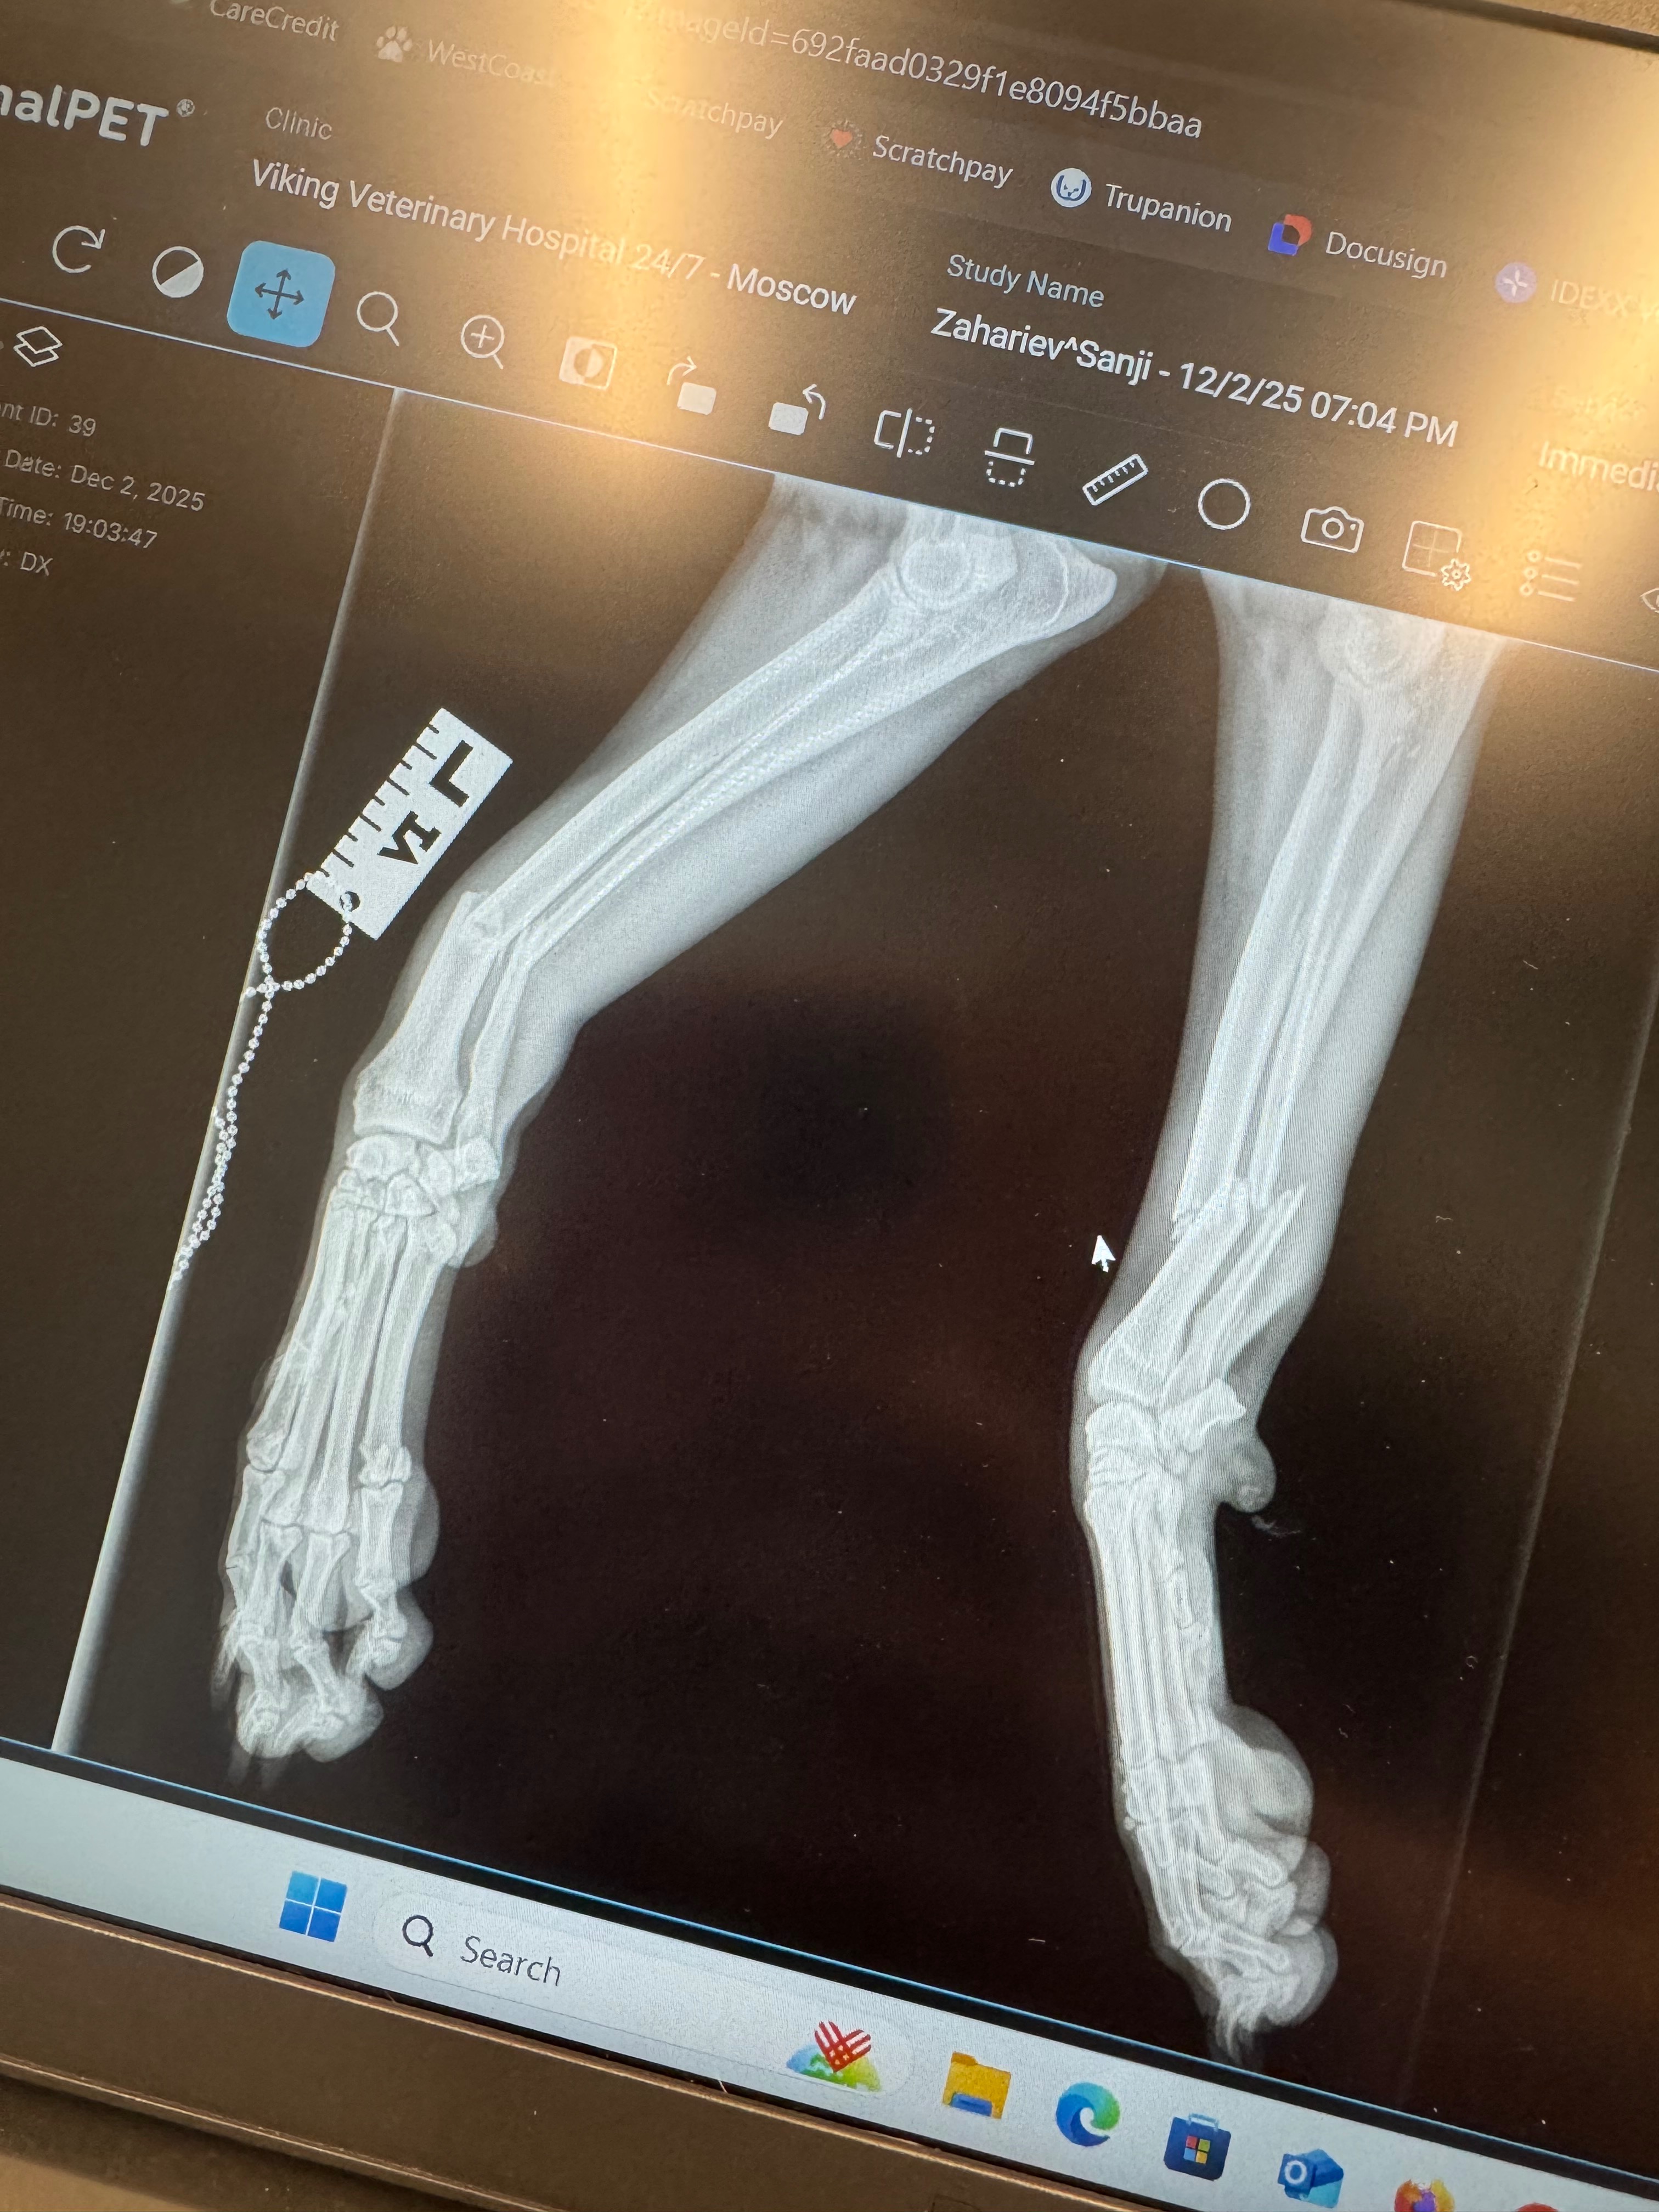

Sanji has been a beloved part of our family since he was a puppy, and now at six years old, he means the world to us and our three young children. On Tuesday evening of December 2nd, Sanji was hit by a bus. The accident left him with staples in his head and shoulder, and both of his front legs were broken—two complete breaks in his left leg and three in his right. The road to recovery will be long and challenging, as Sanji will need surgery involving plates and pins to repair his legs, followed by extensive after care. He had his surgery at PAWS in Moscow and that bill was $7500 along with weekly splint changes for $110 for 8 weeks. The Viking pet hospital bill was $1952…